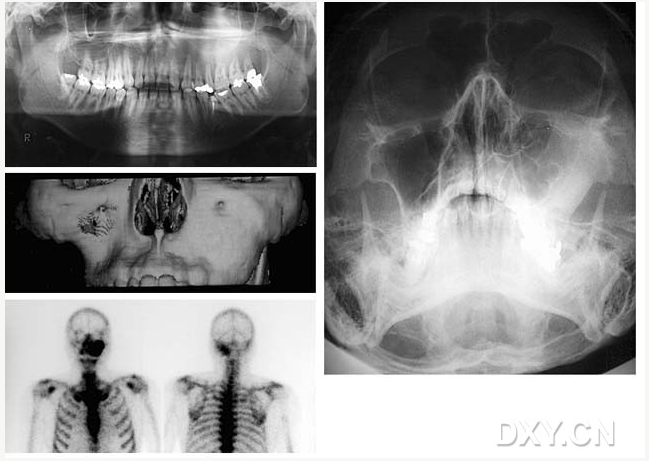

骨肉瘤

鼻竇炎(注意不要誤診呀)

良性成牙骨質(zhì)細胞瘤

頜骨腫瘤